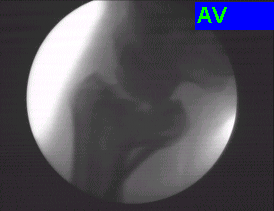

Case:3 Hoffa's Fracture

Pre-Op

Per-Op

Post-Op